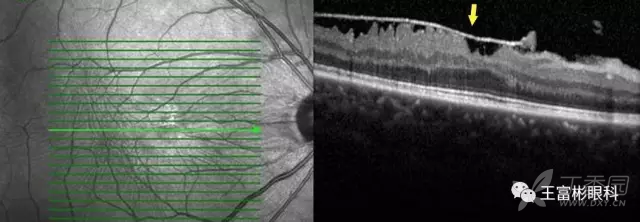

对于黄斑前膜来说,无创的OCT检查是必要的。在上面的图像里,“箭”标示了视网膜前膜反射光带,内界膜由于受到视网膜前膜的影响,失去正常玻璃体视网膜界面的平滑形态,出现皱褶。

右眼术前,OCT显示黄斑前膜,劈裂,神经纤维层增厚,内层视网膜失去正常解剖形态。在IR图像上,可以看到明显的血管迂曲。

右眼术后,显示黄斑前膜很干净的被剥离切除,视网膜厚度由术前的630um降低到术后298um,黄斑区的解剖结构也逐渐接近了正常形态。